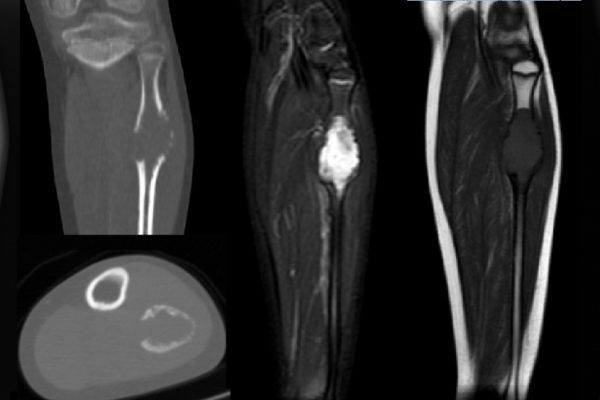

Osteosarkom teşhisi genellikle röntgen, manyetik rezonans görüntüleme (MRG) veya bilgisayarlı tomografi (BT) taramaları ve biyopsi ile konulur. Tedavi genellikle kemoterapi, cerrahi müdahale ve radyoterapiyi içerir. Erken teşhis ve agresif tedavi, prognozu olumlu yönde etkileyebilir.